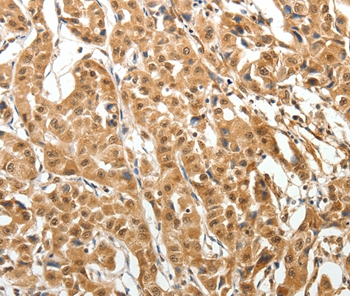

Immunohistochemical analysis of paraffin-embedded Human thyroid cancer tissue using #37265 at dilution 1/40.

,

Immunohistochemical analysis of paraffin-embedded Human lung cancer tissue using #37265 at dilution 1/40.